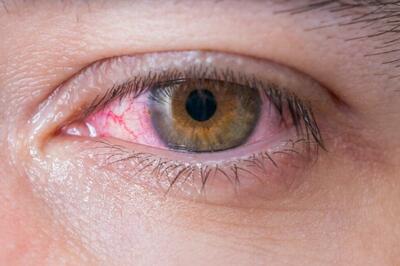

شیوع کرونای چشمی در کشور صحت دارد؟/ توضیحات یک فوق تخصص قرنیه

آیا ماجرای شیوع کرونای چشمی در کشور صحت دارد؟

ماجرای شیوع کرونای چشمی در کشور | روزنو

رئیس بخش عفونی بیمارستان امام خمینی (ره) و نیز متخصص بیماریهای عفونی درخصوص شیوع ویروسی که باعث قرمزی و التهاب چشم میشود و نگرانی مردم را در پی داشته است، توضیح داد.

شیوع کرونای چشمی در کشور/ این ویروس بسیار مسری است - مردم سالاری آنلاین

متخصص بیماری های عفونی گفت: خوشبختانه این ویروس خوشخیم است و معمولا بین ۵ تا ۷ روز بهبود پیدا میکند و احتیاج به مصرف آنتی بیوتیک نیز ندارد و در اغلب بیماران منجر به آسیب به چشم نمیشود.

کرونای چشمی؛ سویه جدید ویروس کرونا! +جزییات و علائم

متخصصان بیماریهای عفونی در بیمارستان امام خمینی (ره) درباره شیوع ویروسی جدید که باعث التهاب و قرمزی چشم میشود، نگرانیها و علائم این بیماری را بررسی کردند.